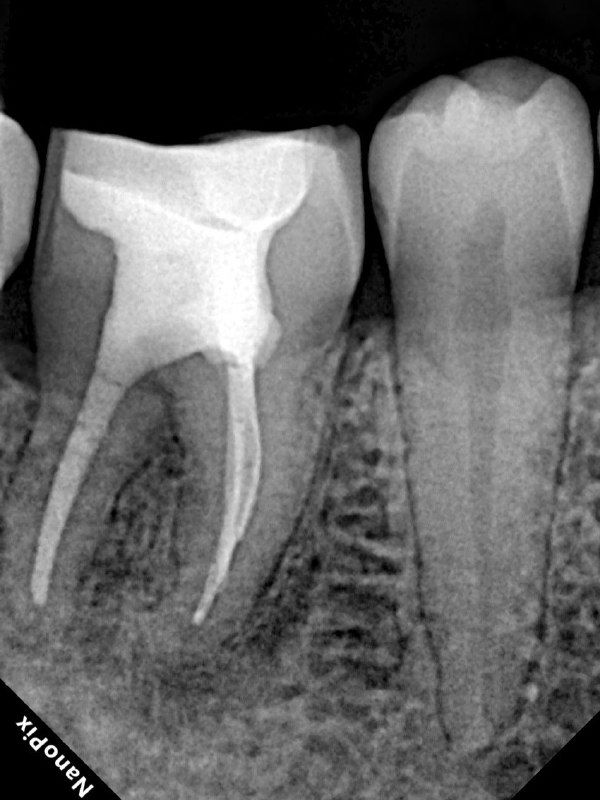

- 1) Обязательно провожу хорошую изоляцию, чтобы была видна полностью коронка зуба. Это важно для создания полости зуба, так как контуры пульпарной камеры повторяют внешние контуры коронки зуба.

- 4)При препарировании каналов стараюсь придерживаться миниинвазивной концепции: в каналах пошире - до чистых дентинных опилок (25,30.04), в тонких корешках может быть и 20.04. за счёт использования активации ирригационных растворов, можно уменьшить размер препарирования.

- 7) Пломбирую вертикальной компакцией гуттаперчи, в то же посещение делаю билдап. А вот коронкой зуб покрывает уже через 6 мес после реколла.